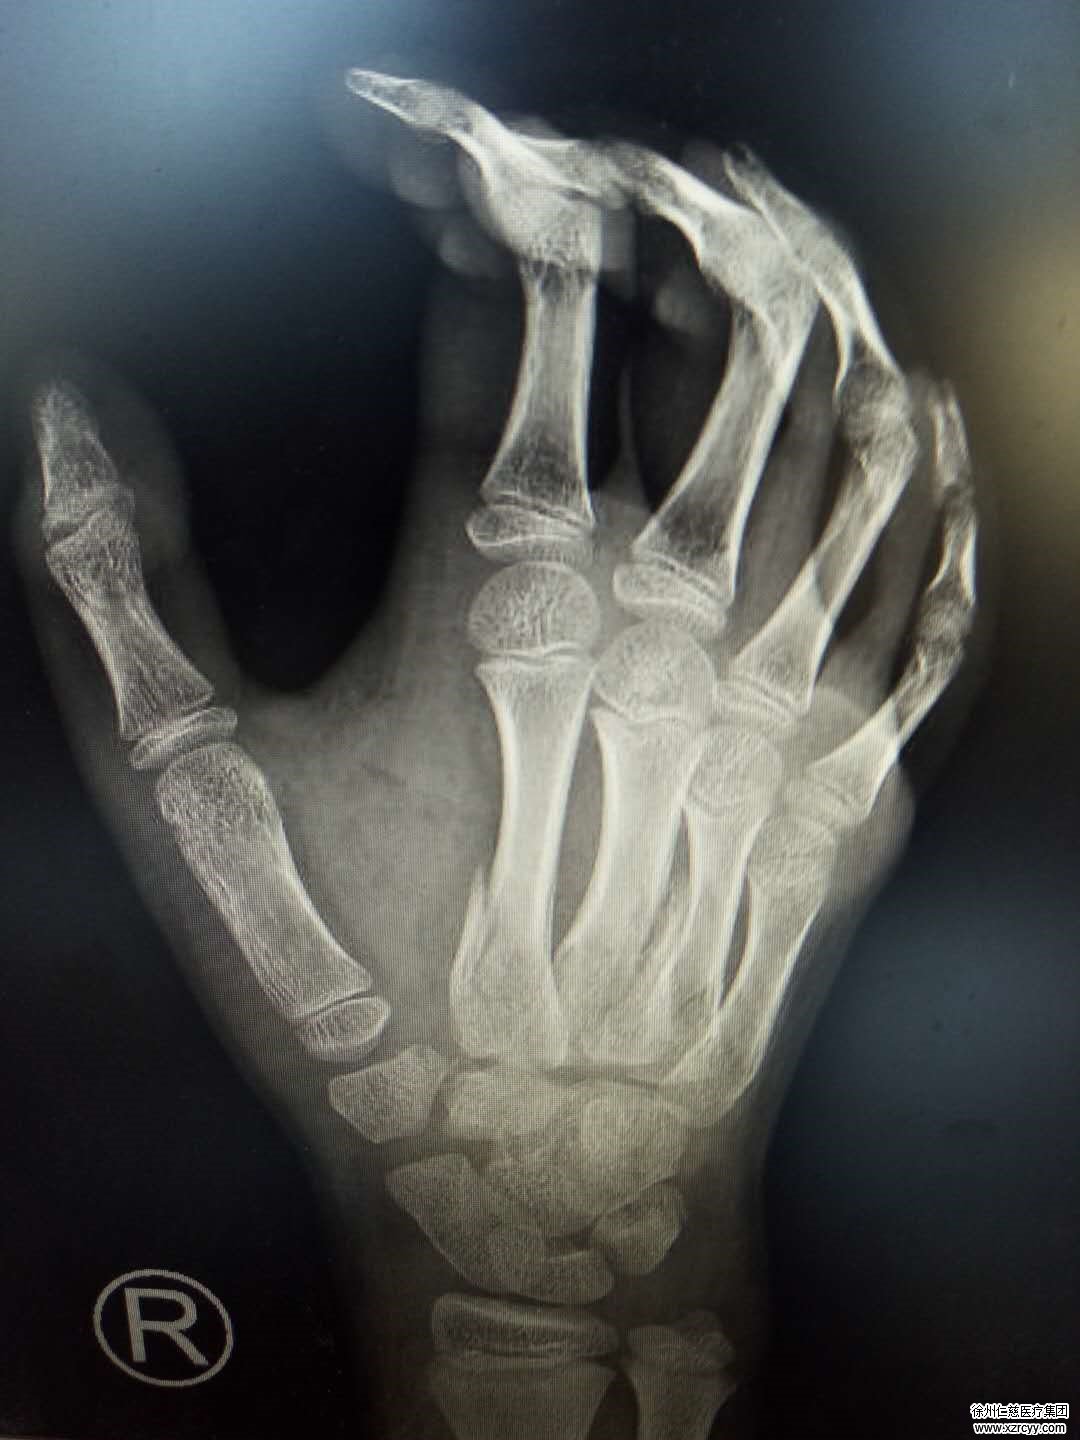

必威官方首页官网betway手外科四病区的郑大伟主任接诊后,发现小硕的右手腕肿胀,手背及腕背部局部皮肤挫伤,右手2/3/4掌骨骨折,腕骨骨折、腕关节脱位外加皮肤挫伤。“这个情况肯定要住院进行手术治疗。”郑主任对小硕的父亲说。

晚上10点34分,小硕被送进了手术室。郑大伟在小硕的右手背第2/4掌骨背侧纵行切口,手掌鱼际纹尺侧向腕部做长约9cm的“S”型切口,分离皮下组织后,发现小硕的切口里存在大量血凝块,祛除淤血后,对张力十分高的肌膜进行切开彻底减压,最后用高分子夹板固定小硕的右手。